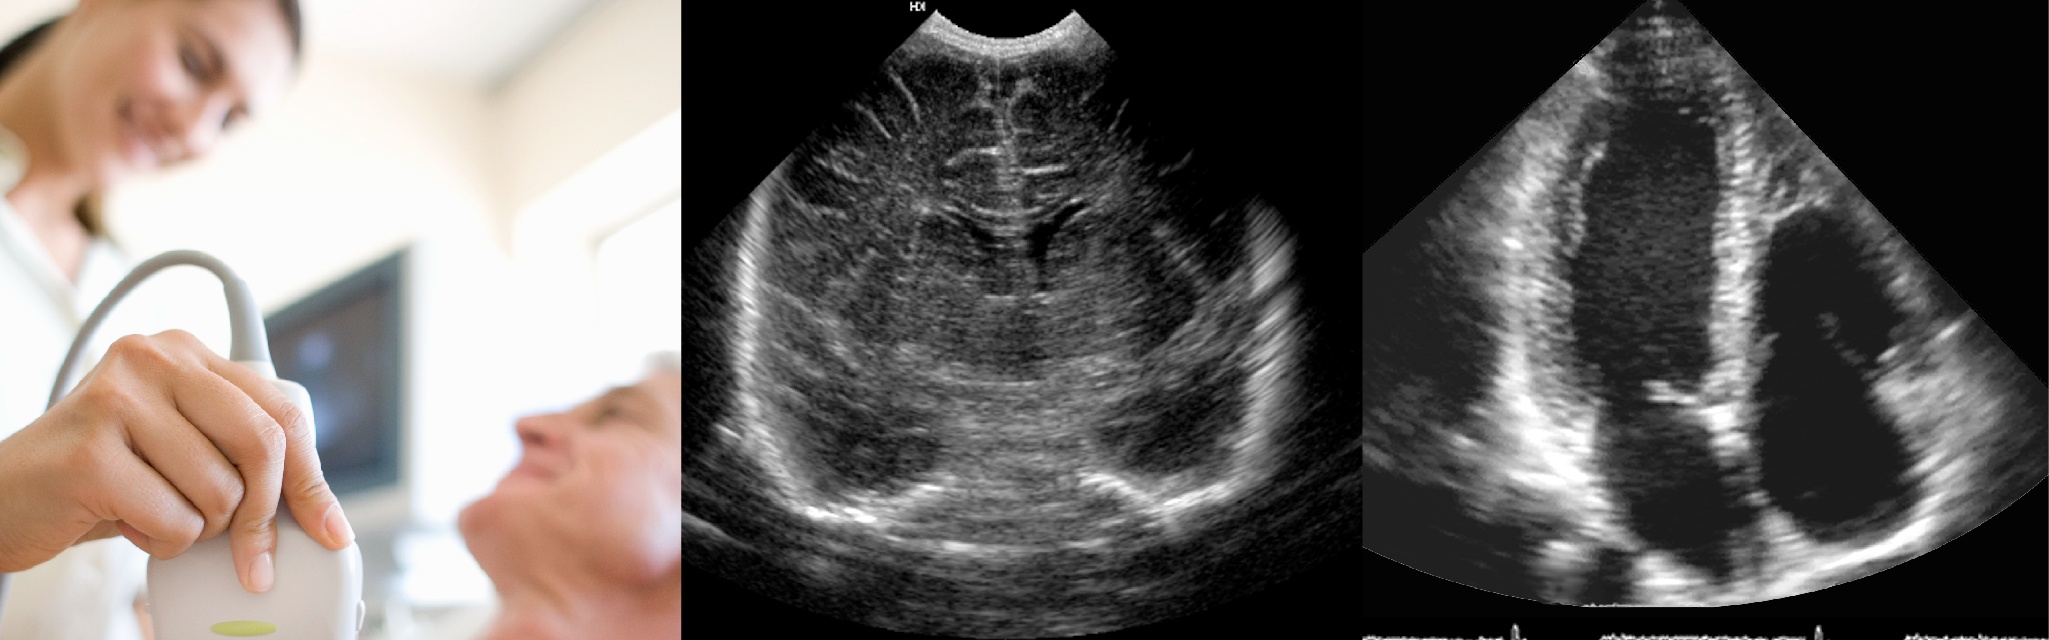

심장 초음파란?

심장초음파는 심장의 움직임과 구조를 평가하는 검사로 심장의 해부학적 구조, 심장

기능, 심장 내 압력 등을 측정할 수 있습니다.

심장 초음파 검사방법

검사는 상의를 벗고 가슴에 심전도 전극을 부착한 후, 탐촉자에 젤을 바르고 시행됩니다.

보다 선명한 영상을 얻기 위해 숨을 내쉰 후 잠시

멈추는 것이 도움이 될 수 있으며, 어린 소아 환자의 경우 검사 진행이 어려울 수 있어 의료진의 판단하에 진정제 사용이 고려될 수 있습니다.

20~30분 정도 소요되며, 인체에 무리를 주지 않는 비침습적 검사로 별도의 준비 없이 시행됩니다.